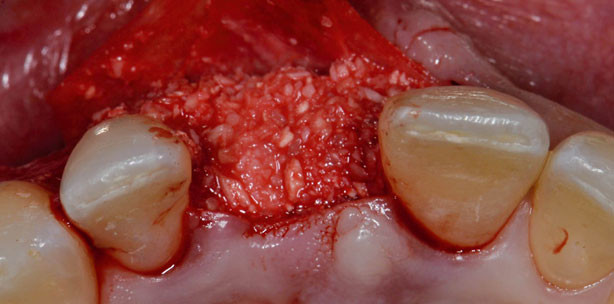

Häufig hat bereits die Zahnextraktion massive Gewebsveränderungen zur Folge. Daher empfiehlt es sich, insbesondere in ästhetisch kritischen Zonen oder in Bereichen mit präoperativ reduziertem Knochenangebot, bei der Zahnextraktion augmentative Verfahren durchzuführen. Die Socket-Preservation-Technik versucht die Veränderungen nach Zahnextraktion zu kompensieren und ist die Bezeichnung für die Auffüllung der Extraktionsalveole mit Biomaterialien zur Stabilisierung des Blutkoagulums und zur Augmentation der Extraktionsalveole. Es konnten bisher positive Ergebnisse hinsichtlich einer vorhersagbaren Knochenneubildung erzielt werden. Ein weiteres Hauptziel ist die Verbesserung der Weichgewebesituation für die folgende Implantation. In diesem Zusammenhang hat sich die Inkorporation eines Bindegewebe-Punches aus dem Gaumen als Mittel der Wahl erwiesen. Dadurch wird die Weichgewebesituation nach Zahnextraktion verbessert und ein stabilisierender und stützender Effekt auf das Weichgewebe ausgeübt (Abb. 1 bis 5).

Im posterioren Anteil des Unterkiefers ist aufgrund der Atrophie des Kieferkamms häufig nur ein begrenztes Knochenvolumen vorhanden. Bei der lateralen Augmentation kann eine Stabilisierung des kortikospongiösen Knochenersatzmaterials über eine flexible kollagenhaltige Knochenmembran erfolgen. Dieser neue Ansatz ermöglicht eine stabile Verankerung des Knochenersatzmaterials und wird zu Eigenknochen umgebaut. Durch die hohe Stabilität bleibt das Knochenmaterial in Position und bildet einen geeigneten Raum für neues einwachsendes Knochengewebe. In einem zweiten Eingriff werden sechs Monate nach der Augmentation Implantate inseriert (Abb. 6 bis 10).

In der ästhetischen Zone ist eine ausreichende Menge an Hart- und Weichgewebe unerlässlich für ein ansprechendes ästhetisches Ergebnis. In vielen Fällen fehlt am bukkalen Aspekt die entsprechende knöcherne Struktur. Die am meisten verbreitete Technik zur Verbesserung der Kieferkammbreite ist die Technik der ­geführten Knochenregeneration (GBR). Die Double-Layer-Technik umfasst die Anwendung zweier unterschiedlicher Membranen in Kombination mit einem xenogenen Knochenersatzmaterial. Die Vorteile einer lagerstabilen Membran, die eine Barrierefunktion von sechs bis acht Monaten gewährleistet, werden kombiniert mit der optimalen Weichgewebeintegration einer zweiten darüberliegenden Membran (Abb. 11 bis 15).